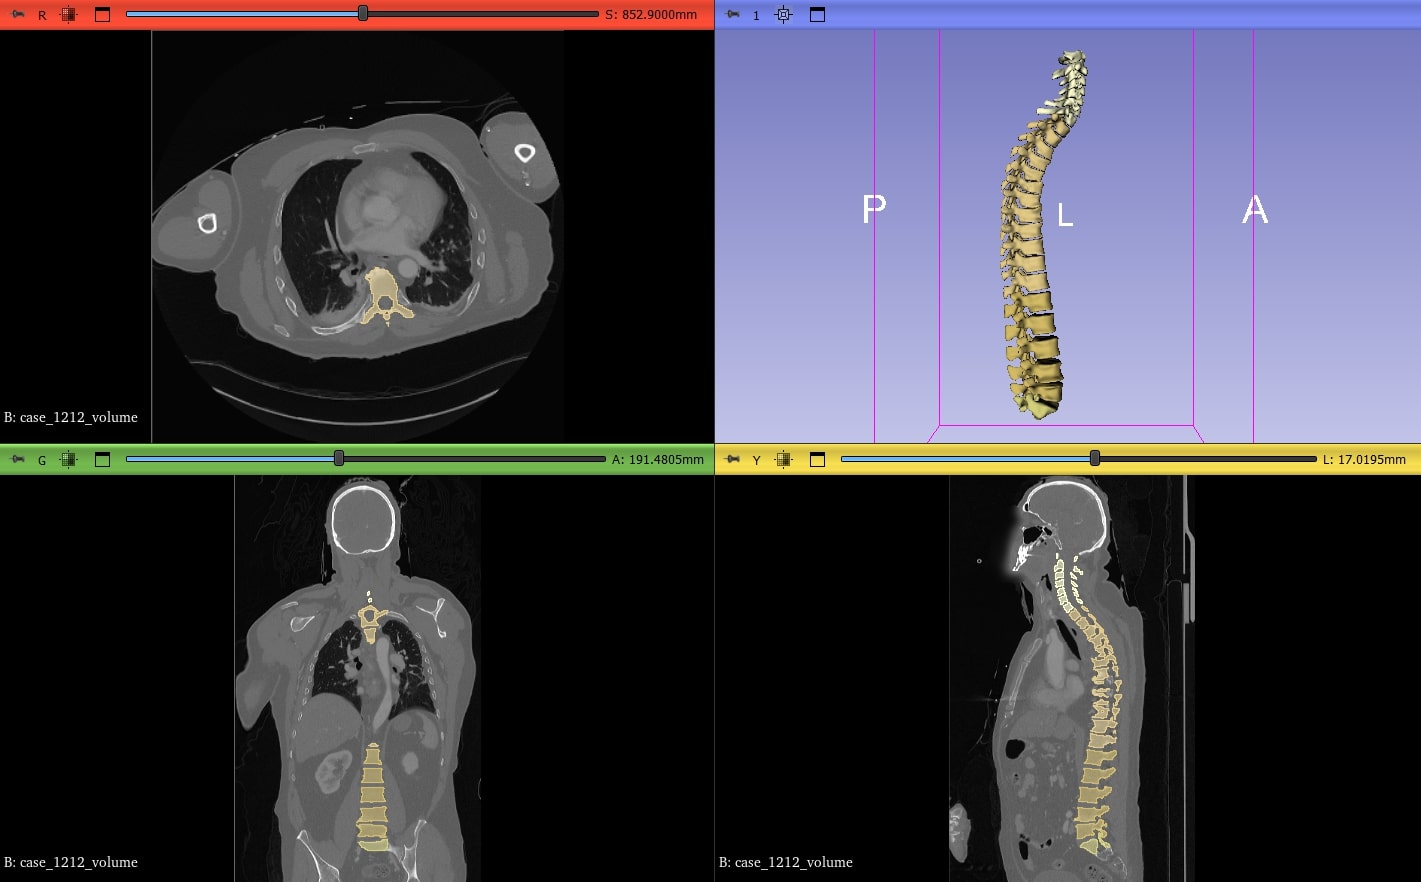

La segmentazione automatica delle vertebre in immagini TC rappresenta un supporto fondamentale per diagnosi, pianificazione chirurgica e analisi morfometriche. L’impiego di tecniche deep learning consente oggi risultati rapidi e accurati, facilitando l’integrazione dell’intelligenza artificiale nei flussi di lavoro clinici. Questo studio valuta le prestazioni dei modelli Vertebrae TS2 e Vertebrae TS2 – Quick, inclusi nel framework MONAI Auto3DSeg, confrontandoli con segmentazioni di riferimento ottenute dal tool TotalSegmentator.

È stato utilizzato un dataset open source contenente immagini TC di 18 pazienti, ciascuna associata a maschere di segmentazione delle 25 vertebre da C1 a S1 pre-generate mediante l’algoritmo TotalSegmentator. Entrambe le versioni degli algoritmi in esame sono state eseguite dall’ambiente 3D Slicer, e le segmentazioni ottenute confrontate con le maschere di riferimento. La valutazione è stata condotta tramite due metriche: indice di Dice (sovrapposizione volumetrica) e distanza media di Hausdorff (distanza spaziale dei contorni).

A livello generale, il modello TS2 ha mostrato prestazioni superiori, con valori medi di Dice intorno a 0.9, mentre TS2 – Quick si attesta prevalentemente tra 0.7 e 0.8. Le distanze di Hausdorff risultano generalmente inferiori a 1 mm per TS2, ma possono aumentare in TS2 – Quick, specialmente nelle vertebre inferiori, come S1, dove sono stati osservati valori fino a circa 3.9 mm. È stato inoltre eseguito un test statistico di Wilcoxon per dati appaiati sui valori di Dice, che ha evidenziato una differenza significativa tra i due modelli (p-value << 0.001). I tempi di segmentazione, rilevati sulla stessa workstation equipaggiata con GPU, si attestano attorno ai 15–20 secondi per l’algoritmo Quick e tra 1 e 2 minuti per TS2, a conferma del diverso impatto computazionale.